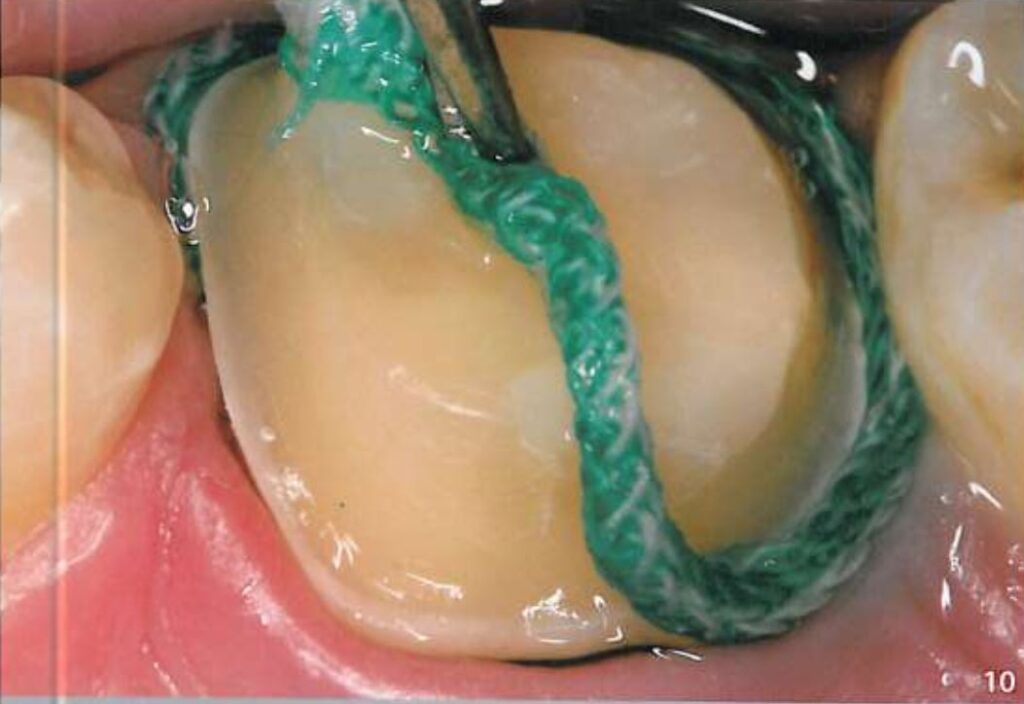

Khi chuẩn bị lấy dấu, phải thổi khô dịch và nước bọt xung quanh, sau đó gắp sợi chỉ ở trên ra (H10).

Ngay lập tức bơm cao su lỏng vào khe nướu (H11).

Gắp sợi chỉ còn lại ở trong ra.